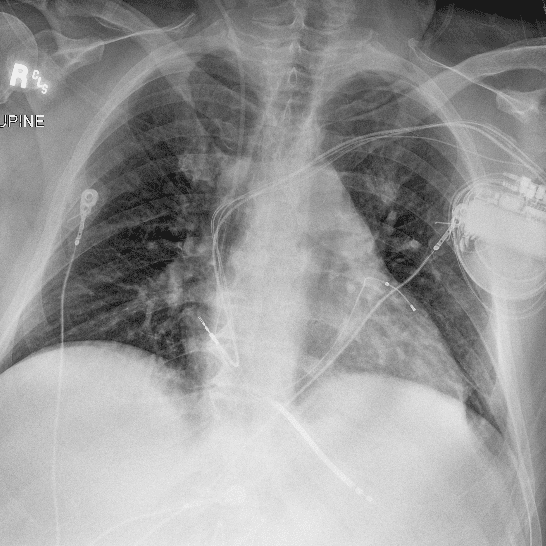

Practice Cases